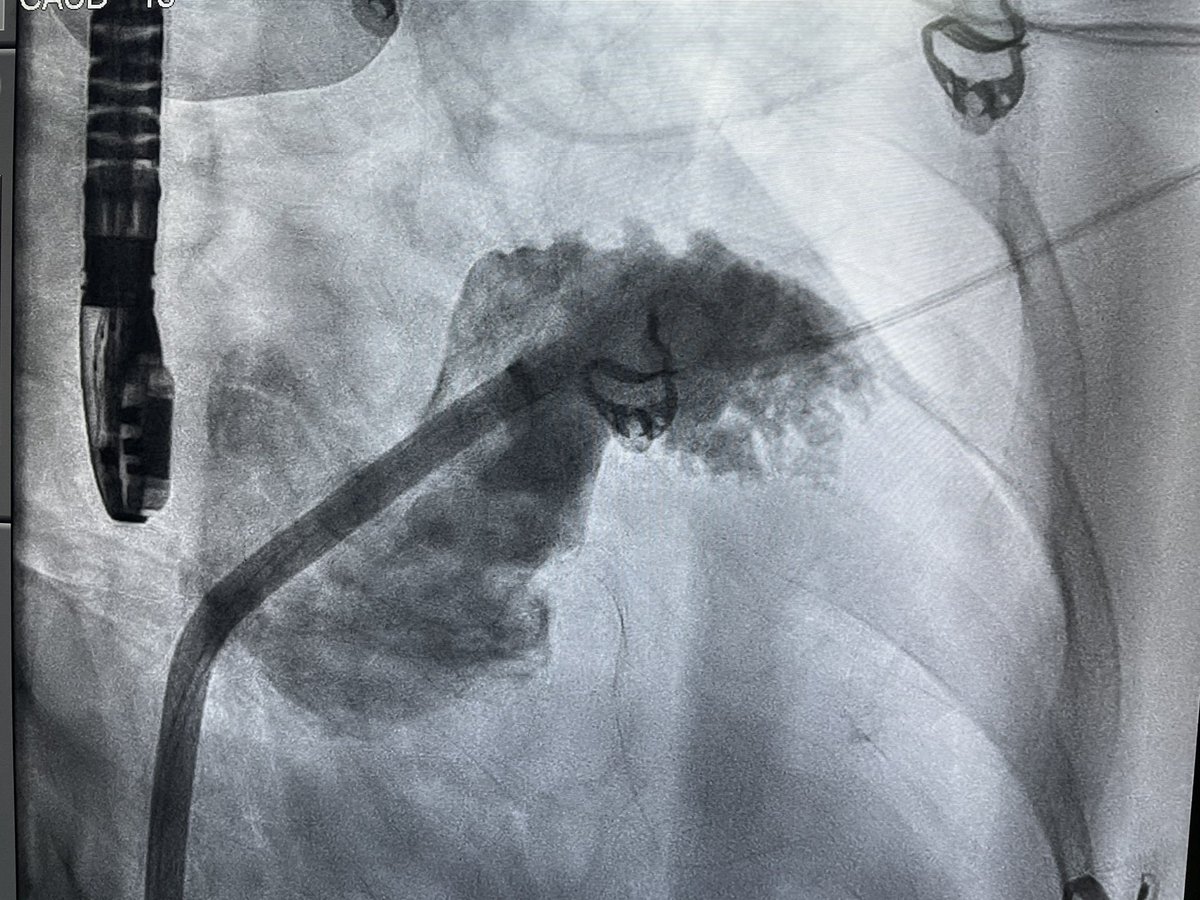

Dual chamber Leadless AVEIR pacemaker at Apollo Chennai - first in Tamilnadu and Apollo Group. - innovative, revolutionary, minimally invasive solution that ensures faster recovery and lasting comfort with physiological pacing. @Pacemaker @Apollo_Chennai @AbbottNews